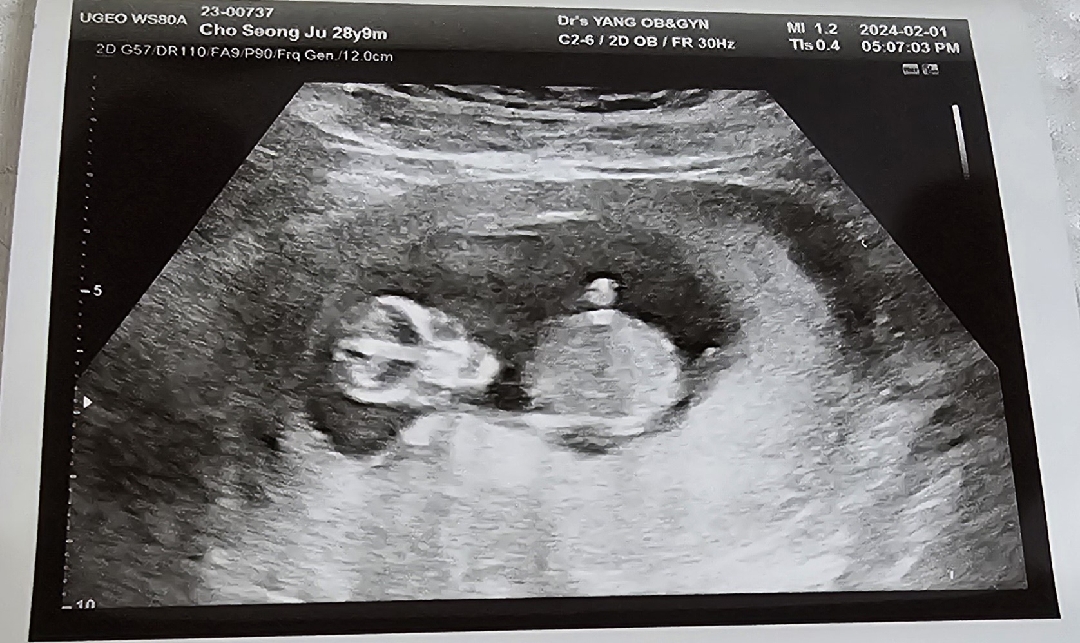

12주 5일 각도법 성별 알 수있을까요?

딸일까요? 아들일까요? 너무 궁금 해요!

앞모습이라서 각도를 못봐요